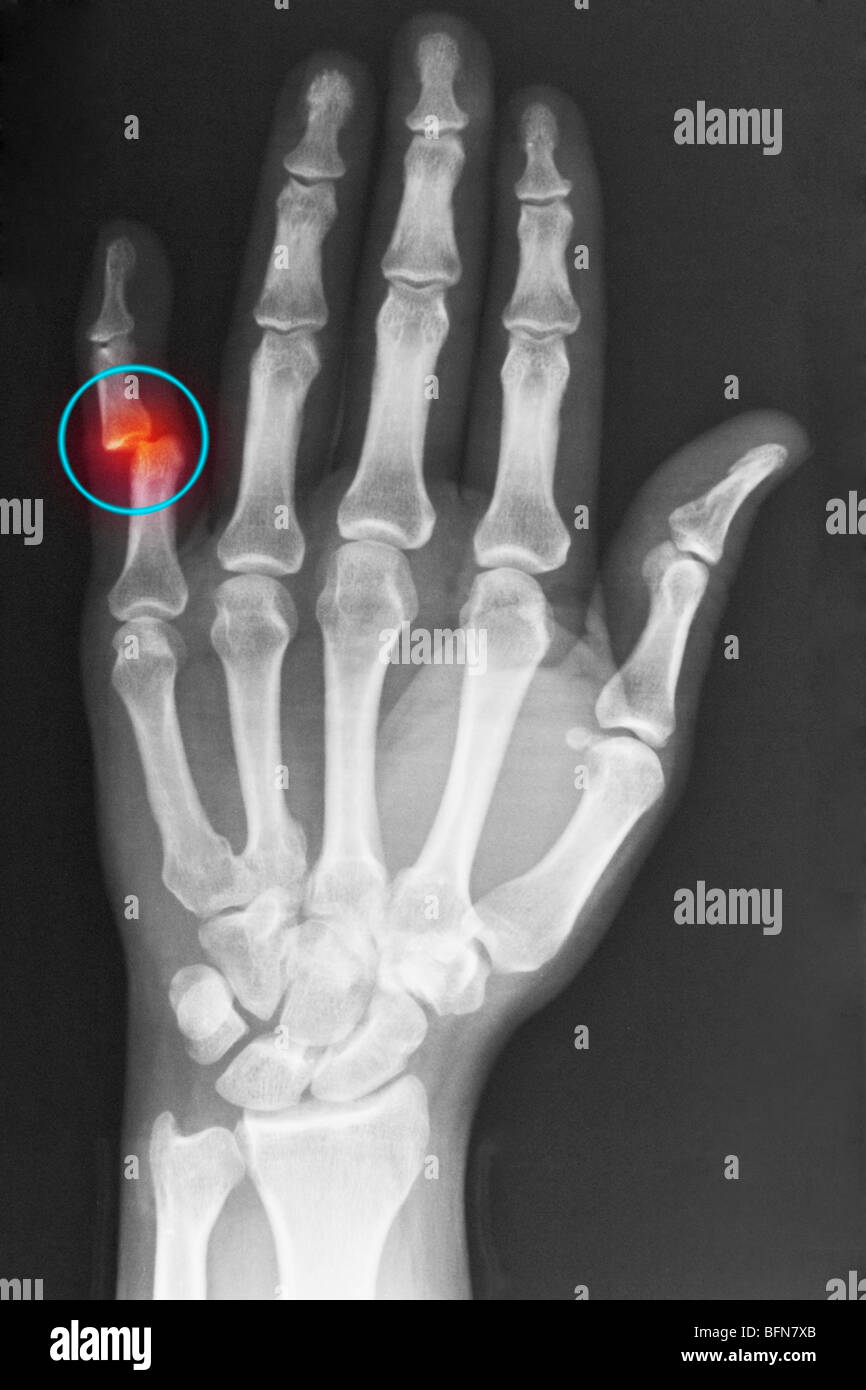

From www.alamy.com

hand xray showing a dislocation of the proximal interphalangeal joint Dip Joint Dislocation Dip joint dislocations are less common and are usually due to a crush injury in which an object (e.g., baseball) hits the finger, causing the dip joint to hyperextend or hyperflex. Simple closed dip joint dislocations can be mobilized early and should get a good outcome with minimal loss of rom and residual deformity. There are three types of finger. Dip Joint Dislocation.